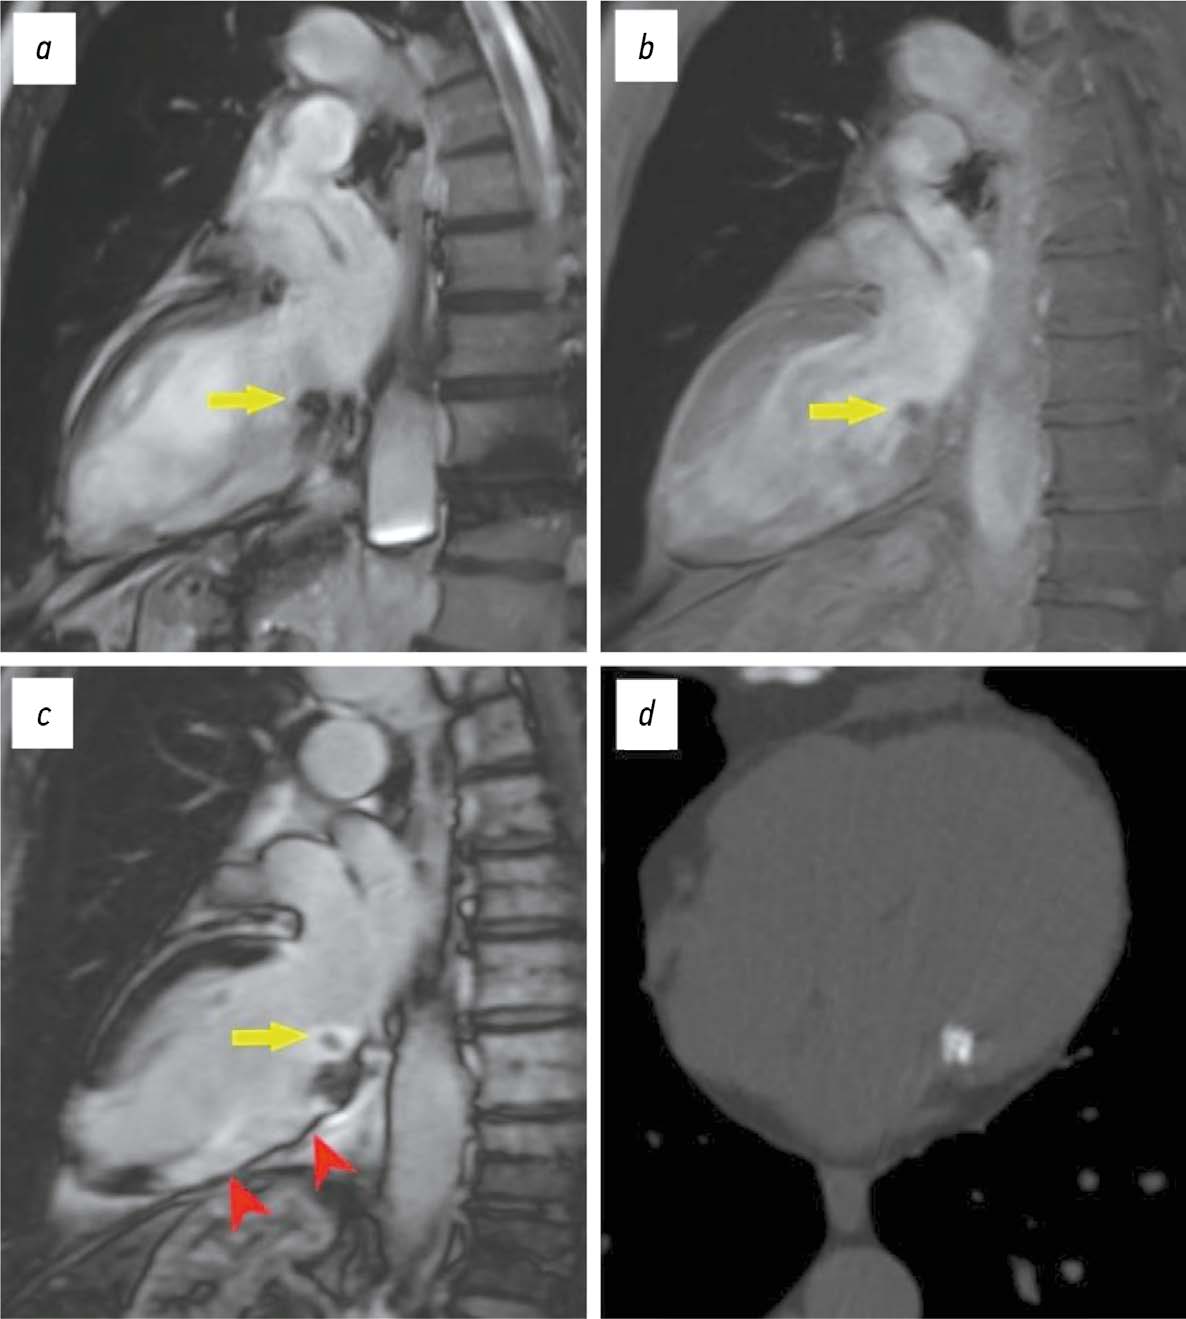

The differential diagnosis of an echocardiographically detected intracardiac mass in the mitral annulus can be challenging and usually requires a multimodal approach. This type of lesion is very often associated with subvalvular calcification of the mitral valve. The rare, caseous, variant is the most difficult to diagnose. This case series highlights the clinical significance of computed tomography in detecting and characterizing subvalvular mitral annular calcification when other modalities, particularly echocardiography, are inconclusive. The aim of this article was to raise awareness among specialists of the classic signs of caseous subvalvular calcification of the mitral annulus when visualized with different modalities. Special attention is also given to providing a differential diagnostic series that identifies features that differentiate subvalvular calcification of the mitral annulus from other conditions at this site. Healthcare professionals need to be aware of these mitral valve lesions in order to predict possible associated complications and plan a treatment strategy that may help avoid unnecessary surgical procedures in some cases.